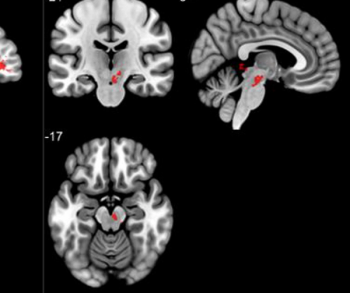

Recently launched at the Radiological Society of North America (RSNA) conference, the SIGNA Experience reportedly features synergistic technologies and artificial intelligence (AI) advances that help improve the efficiency and quality of magnetic resonance imaging.